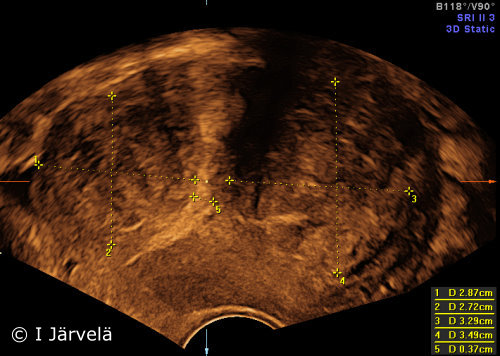

Intramural Myomas (Ultrasound Scan)

Intramural myomas (ultrasound scan).

Picture: Ilkka Järvelä; text: Dimitrios Scordas